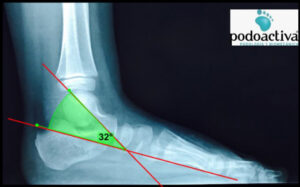

A nivel radiológico se pueden obtener medidas alteradas de diversos ángulos en proyecciones dorsoplantar y sagital. Prestaremos especial atención al ángulo radiográfico sagital TAMBA:

– El ángulo del eje del astrágalo con la base del primer metatarsiano (TAMBA):

– Entre 30º y 60º lo consideraremos astrágalo oblicuo.

– Valores por encima de 60º los consideraremos astrágalo vertical.